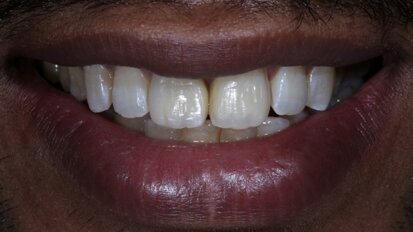

Bringing anterior direct composite restorations to life with histologic layering protocols

Composite resin is a material that is able to mimic natural tooth structure, its optical properties and aesthetics. Often due to trauma or caries, the ...